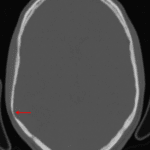

CT

- Mixed attenuation mass with internal calcification centered in the posterior right temporal lobe

- Associated mass effect on the right lateral ventricle without midline shift or hydrocephalus

- Scalloping of the adjacent inner table of the calvarium

Pleomorphic xanthoastrocytoma (PXA)